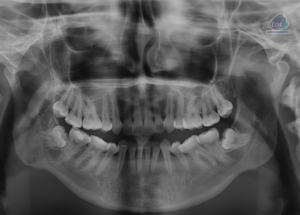

Paciente femenina de 36 años, es referido al Instituto de Diagnóstico Maxilofacial – IDM (Sede Surco) para evaluación de pieza 46 con tratamiento endodóntico. Radiografia